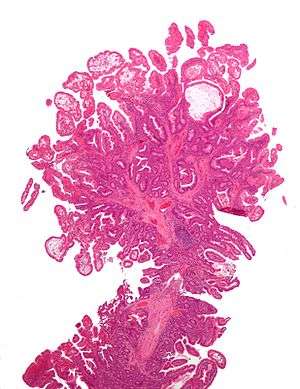

| Micrograph of Peutz-Jeghers type colonic polyp. H&E stain. | |

- Hamartomatous polyps in the gastrointestinal tract. These are benign polyps with an extraordinarily low potential for malignancy.